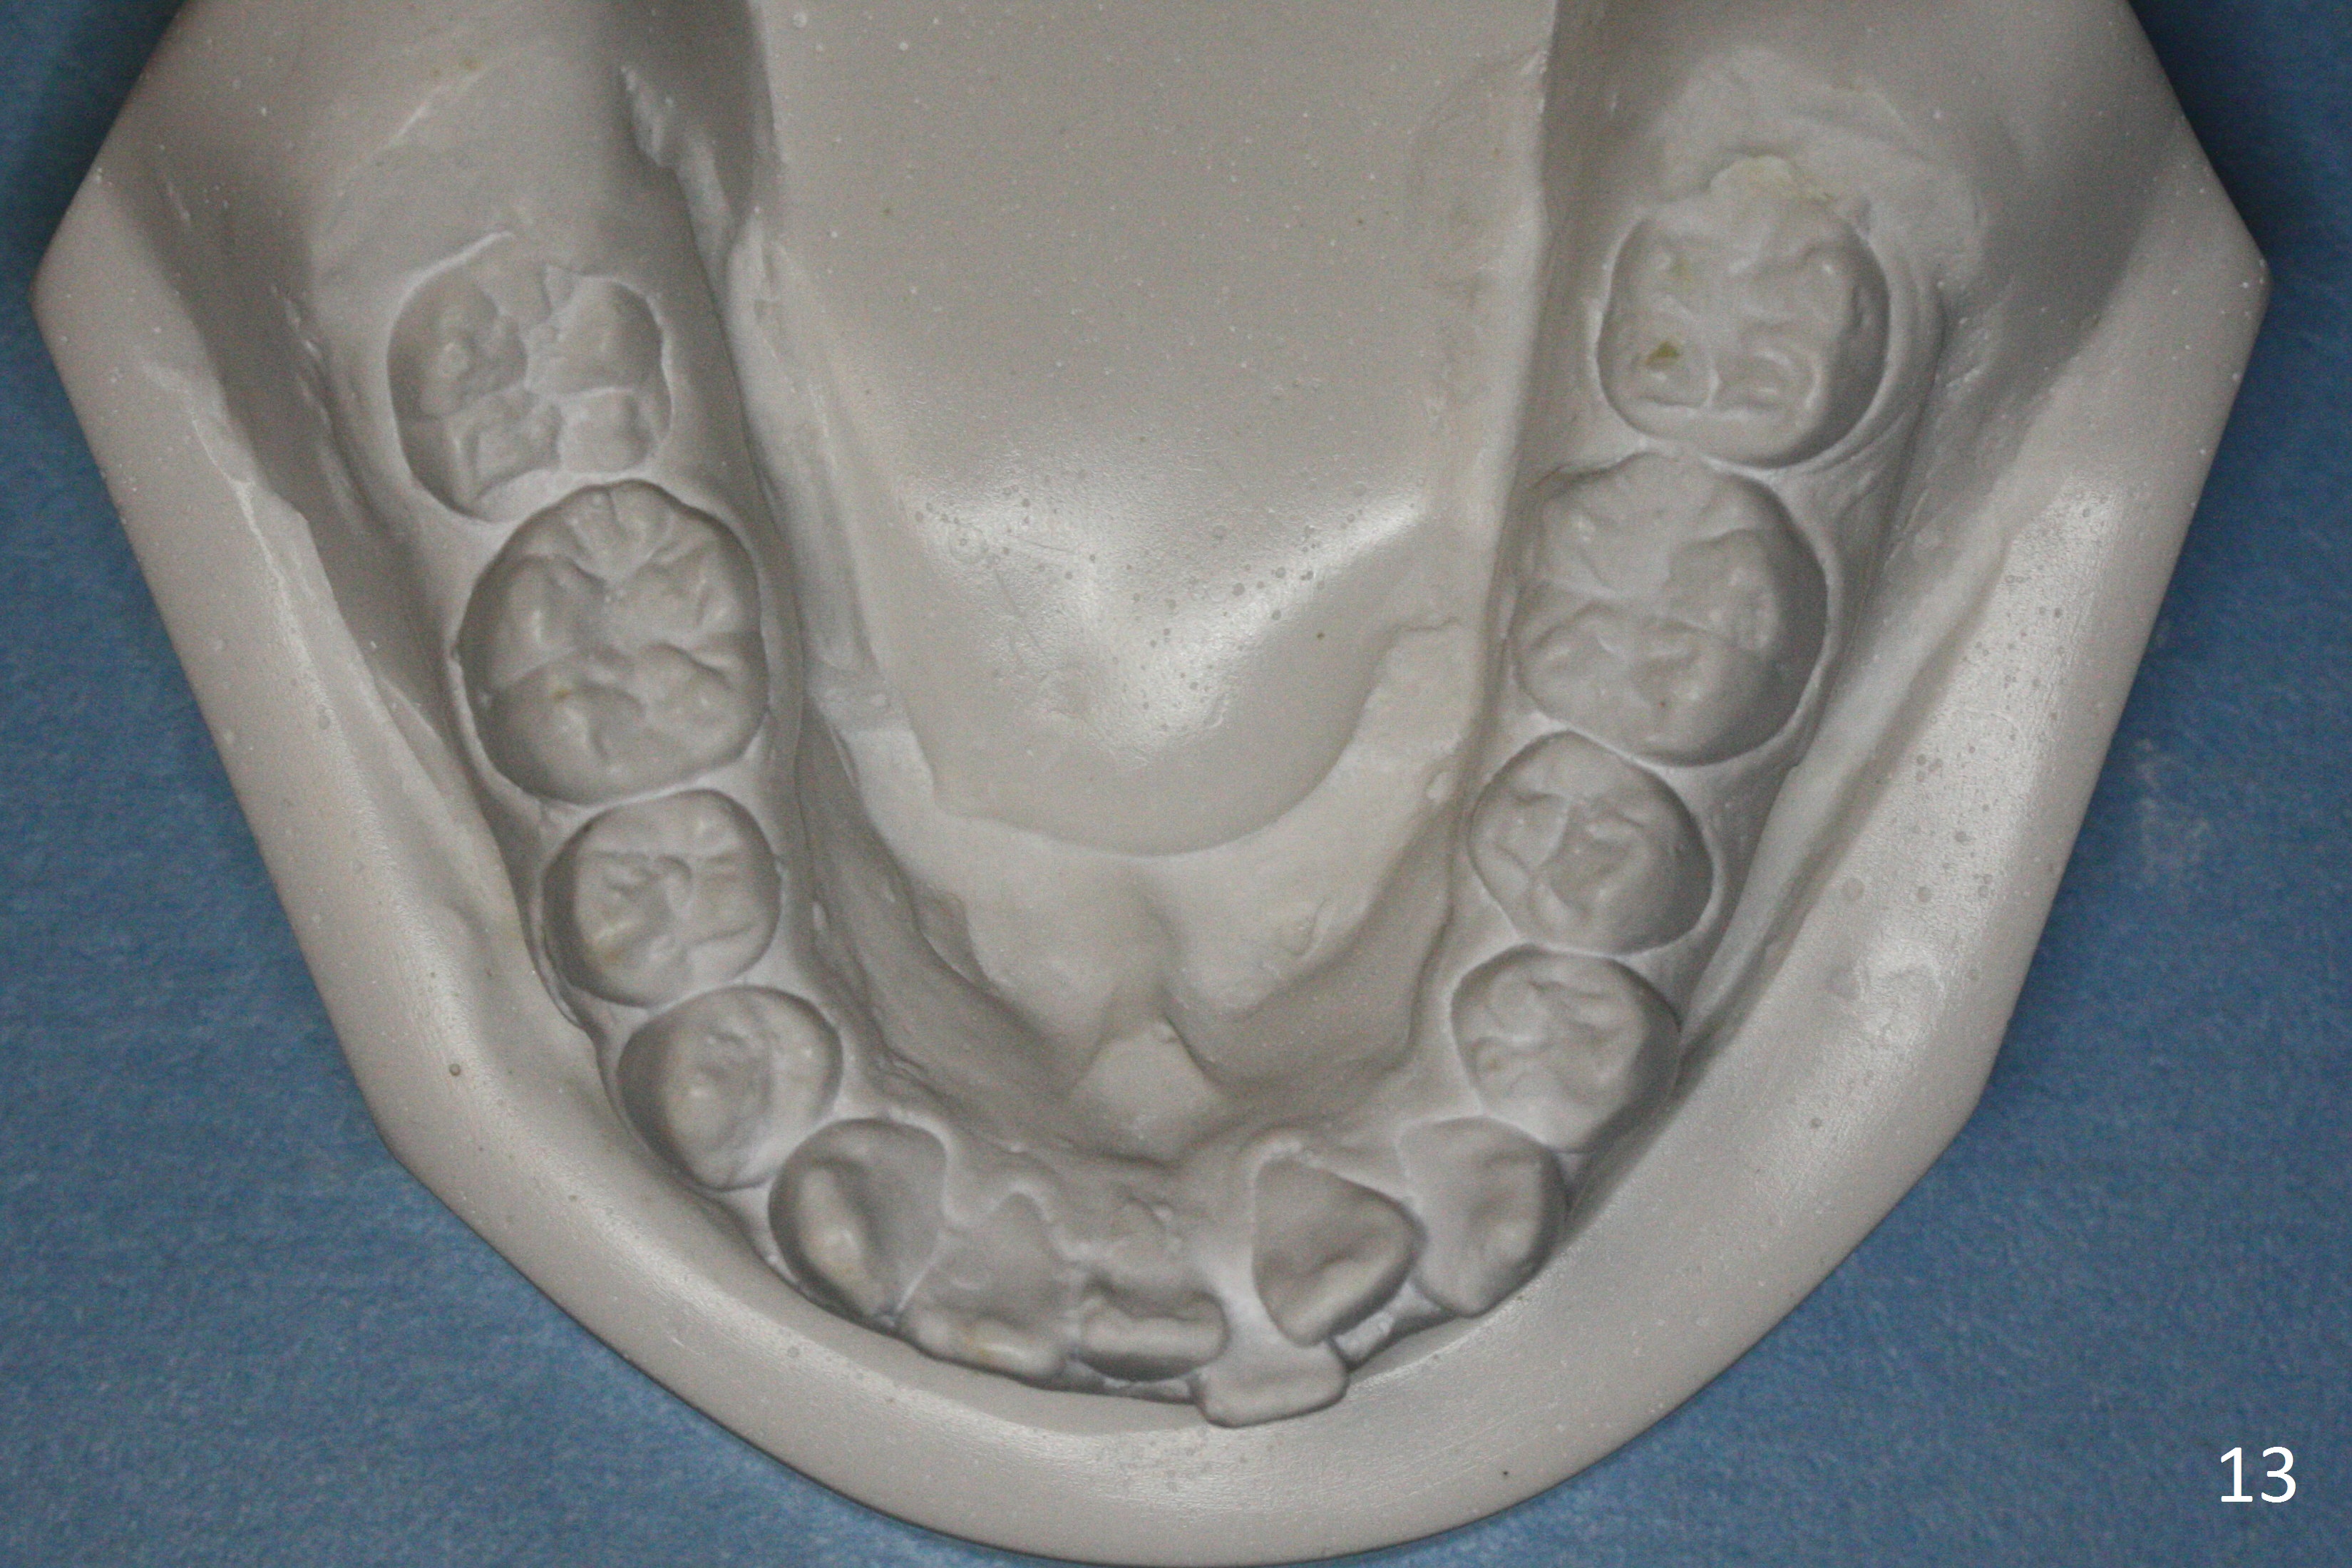

By looking at preop models (Fig.8-13), do you think whether extraction is a better option than non-extraction? Class II occlusion on the right (Fig.8), Class I on the left (Fig.10). With extraction of the 1st bicuspids, the posterior occlusion could be normal with further anterior protrusion (Fig.11). The upper arch is rounded (Fig.12); without extraction, the arch may turn out to be U-shaped. The lower arch is more crowded (Fig.13). Without space, the lower right 2nd molar may not be uprighted (Fig.7).